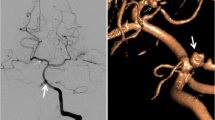

The underlying reason for this significantly higher risk of intracranial aneurysm formation in NPC patients receiving RT may be related to the higher radiation dose to intracranial vessels during RT (Fig. 3). The clinical target volume (CTV) in NPC patients includes the entire nasopharynx, posterior third of the nasal cavity, the maxillary sinus, pterygoid fossae, parapharyngeal space, retropharyngeal lymph nodes, clivus, skull base, sphenoid sinus, and bilateral neck lymph nodes [44, 45]. For other head and neck cancers, the CTV rarely included the clivus, skull base, and sphenoid sinus unless a tumor is involved. Therefore, the intracranial vessels of the majority of NPC patients received a high radiation dose, especially the vessels in the cavernous sinus. In contrast, few non-NPC patients received high radiation doses to the intracranial vessels.

a Nasopharyngeal cancer, cT3N2M0, stage III. A 60-Gy dose was prescribed to the entire nasopharynx, posterior third of the nasal cavity and maxillary sinus, pterygoid fossae, parapharyngeal space, retropharyngeal lymph nodes, clivus, skull base, sphenoid sinus, and bilateral upper neck lymph nodes. A 70-Gy dose was prescribed to the gross tumor and lymphadenopathies areas (red area). b Supraglottic cancer, cT3N0M0, stage III. A 50-Gy dose was prescribed to the retropharyngeal lymph nodes and bilateral neck lymph nodes. A 70-Gy dose was prescribed to the gross tumor area (red area)